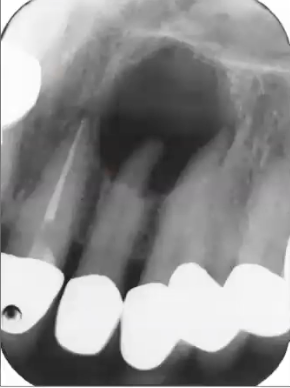

What is this pano showing?

Expansion, subtle sunburst appearance, spiking resorption of 1st molar; seen in osteosarcoma

What is this PA showing?

Widening of PDL seen in osteosarcoma